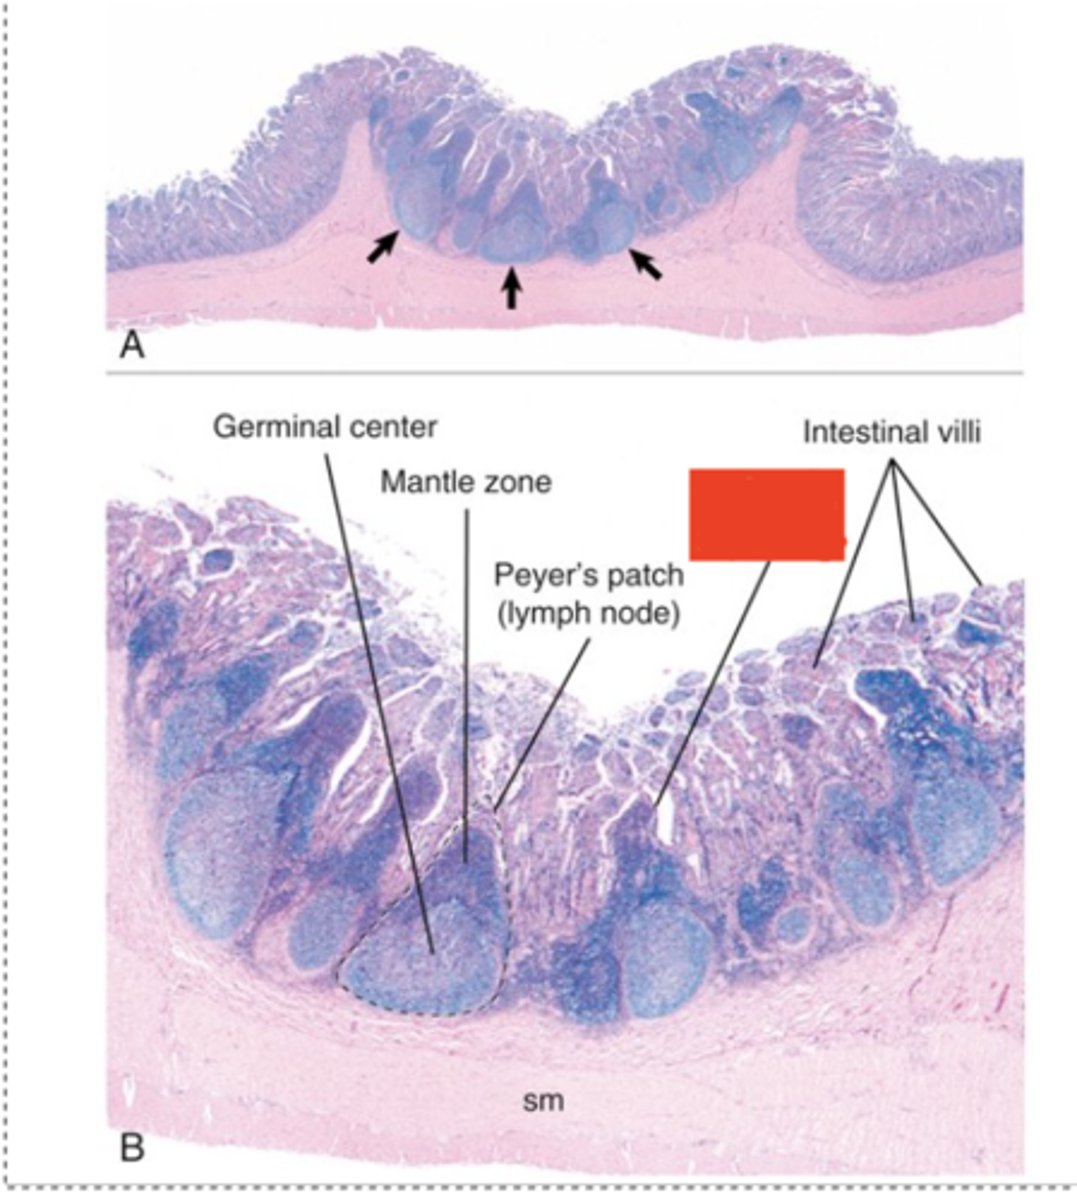

M cells

What type of cell indicated by the red box functions to transfer antigens across the mucosa to dendritic cells and immune cells in the nodule ?